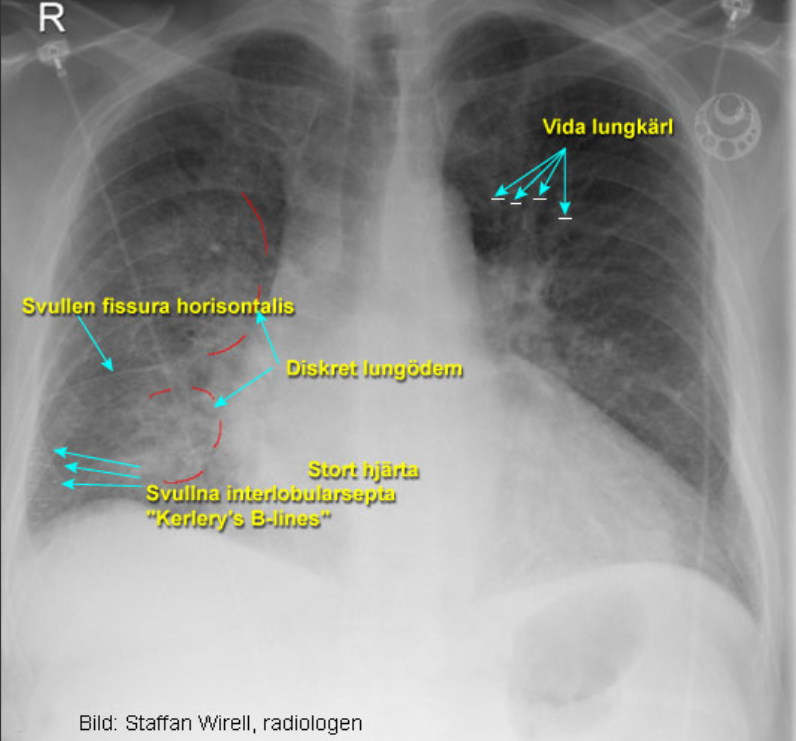

Lungödem och normal lunga